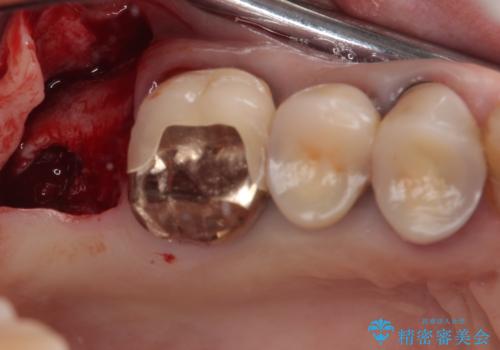

- 食事が取れないほどの激痛で、インプラント治療を希望して来院された患者様です。

近医にてクラウンを除去してもらった状態での来院でした。

遠心が歯根破折しており、歯槽骨が著しく吸収している状態であったため、抜歯即時でのインプラント埋入は断念し、2ヶ月ほど待機してから埋入することとしました。